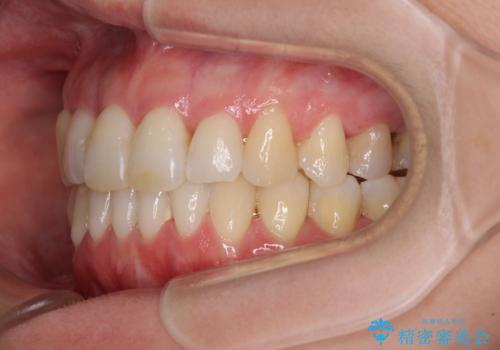

- 奥歯の咬み合わせを気にして来院された患者様です。

上顎骨の幅が下顎骨よりも小さいので、拡大装置により骨幅を広げて上下関係を改善し、その後インビザラインにて歯並びを整えることとしました。

上下の骨幅を改善したことで、スムーズに歯列矯正を行うことができました。

奥歯の咬み合わせを改善する必要があったため、治療は長期化しましたが、きっちりと仕上げることができました。